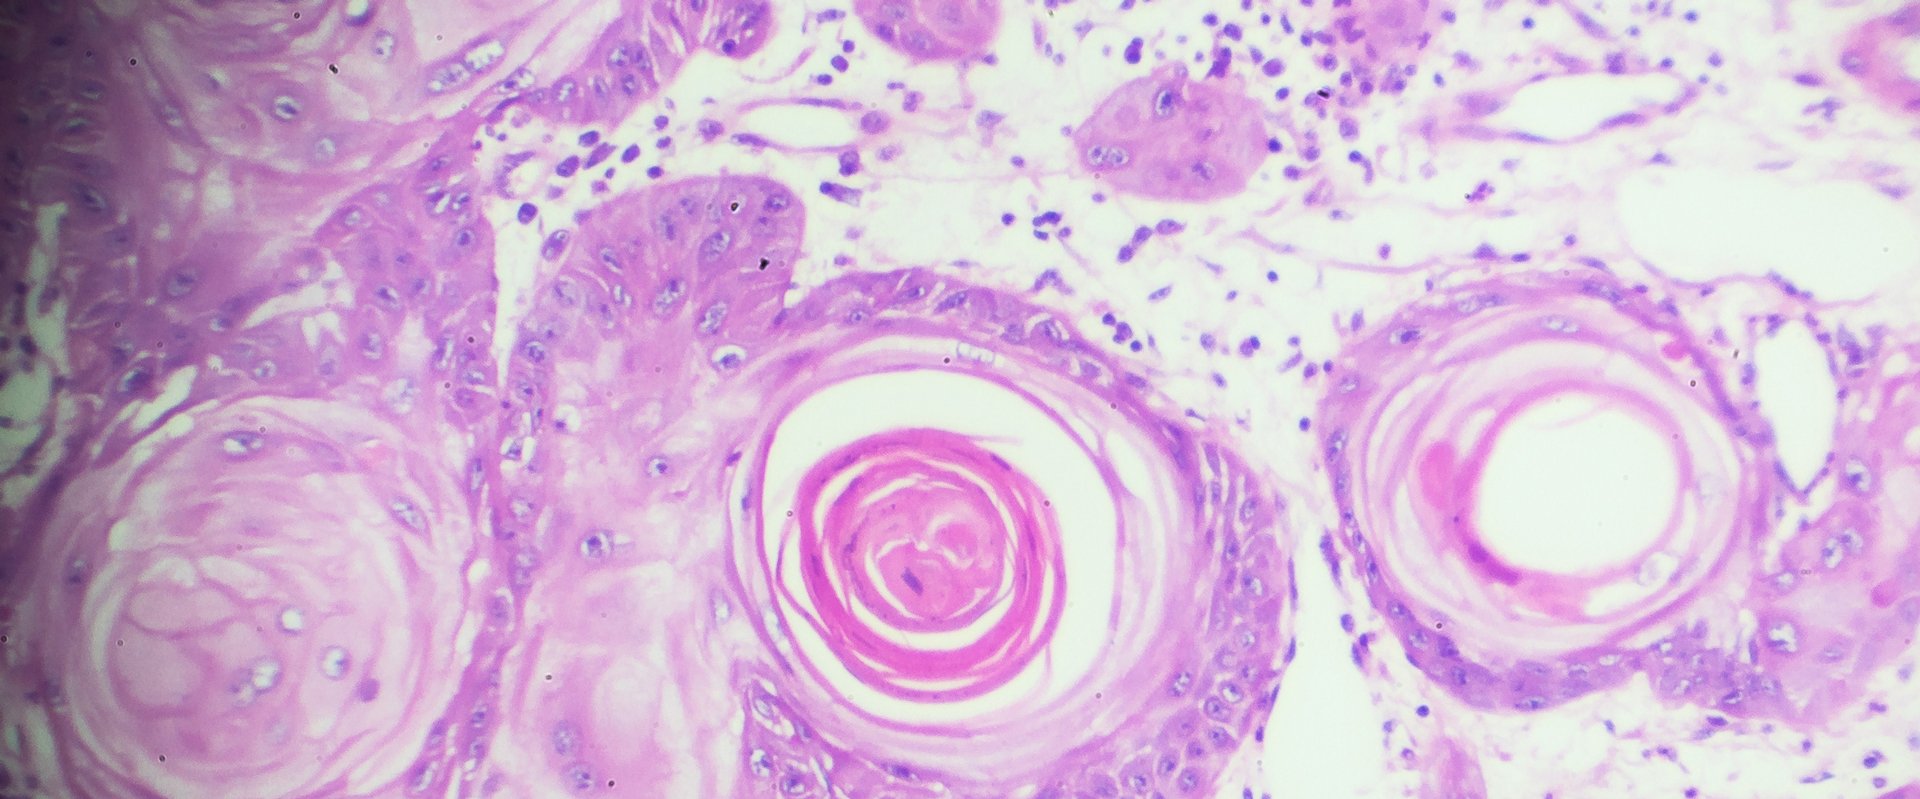

The researchers designed and screened over 100 compounds and identified the drug NFX-179 that fit their requirements. They performed a series of pre-clinical experiments in mouse models and discovered that a gel formulation of NFX-179 reduced the formation of new cutaneous squamous cell carcinomas by up to 92% at the highest doses. Additionally, the effects of the NFX-179 gel were localized, as inhibition of cutaneous squamous cell carcinoma development was observed only in areas that were treated with the drug, and no systemic toxicities were observed.